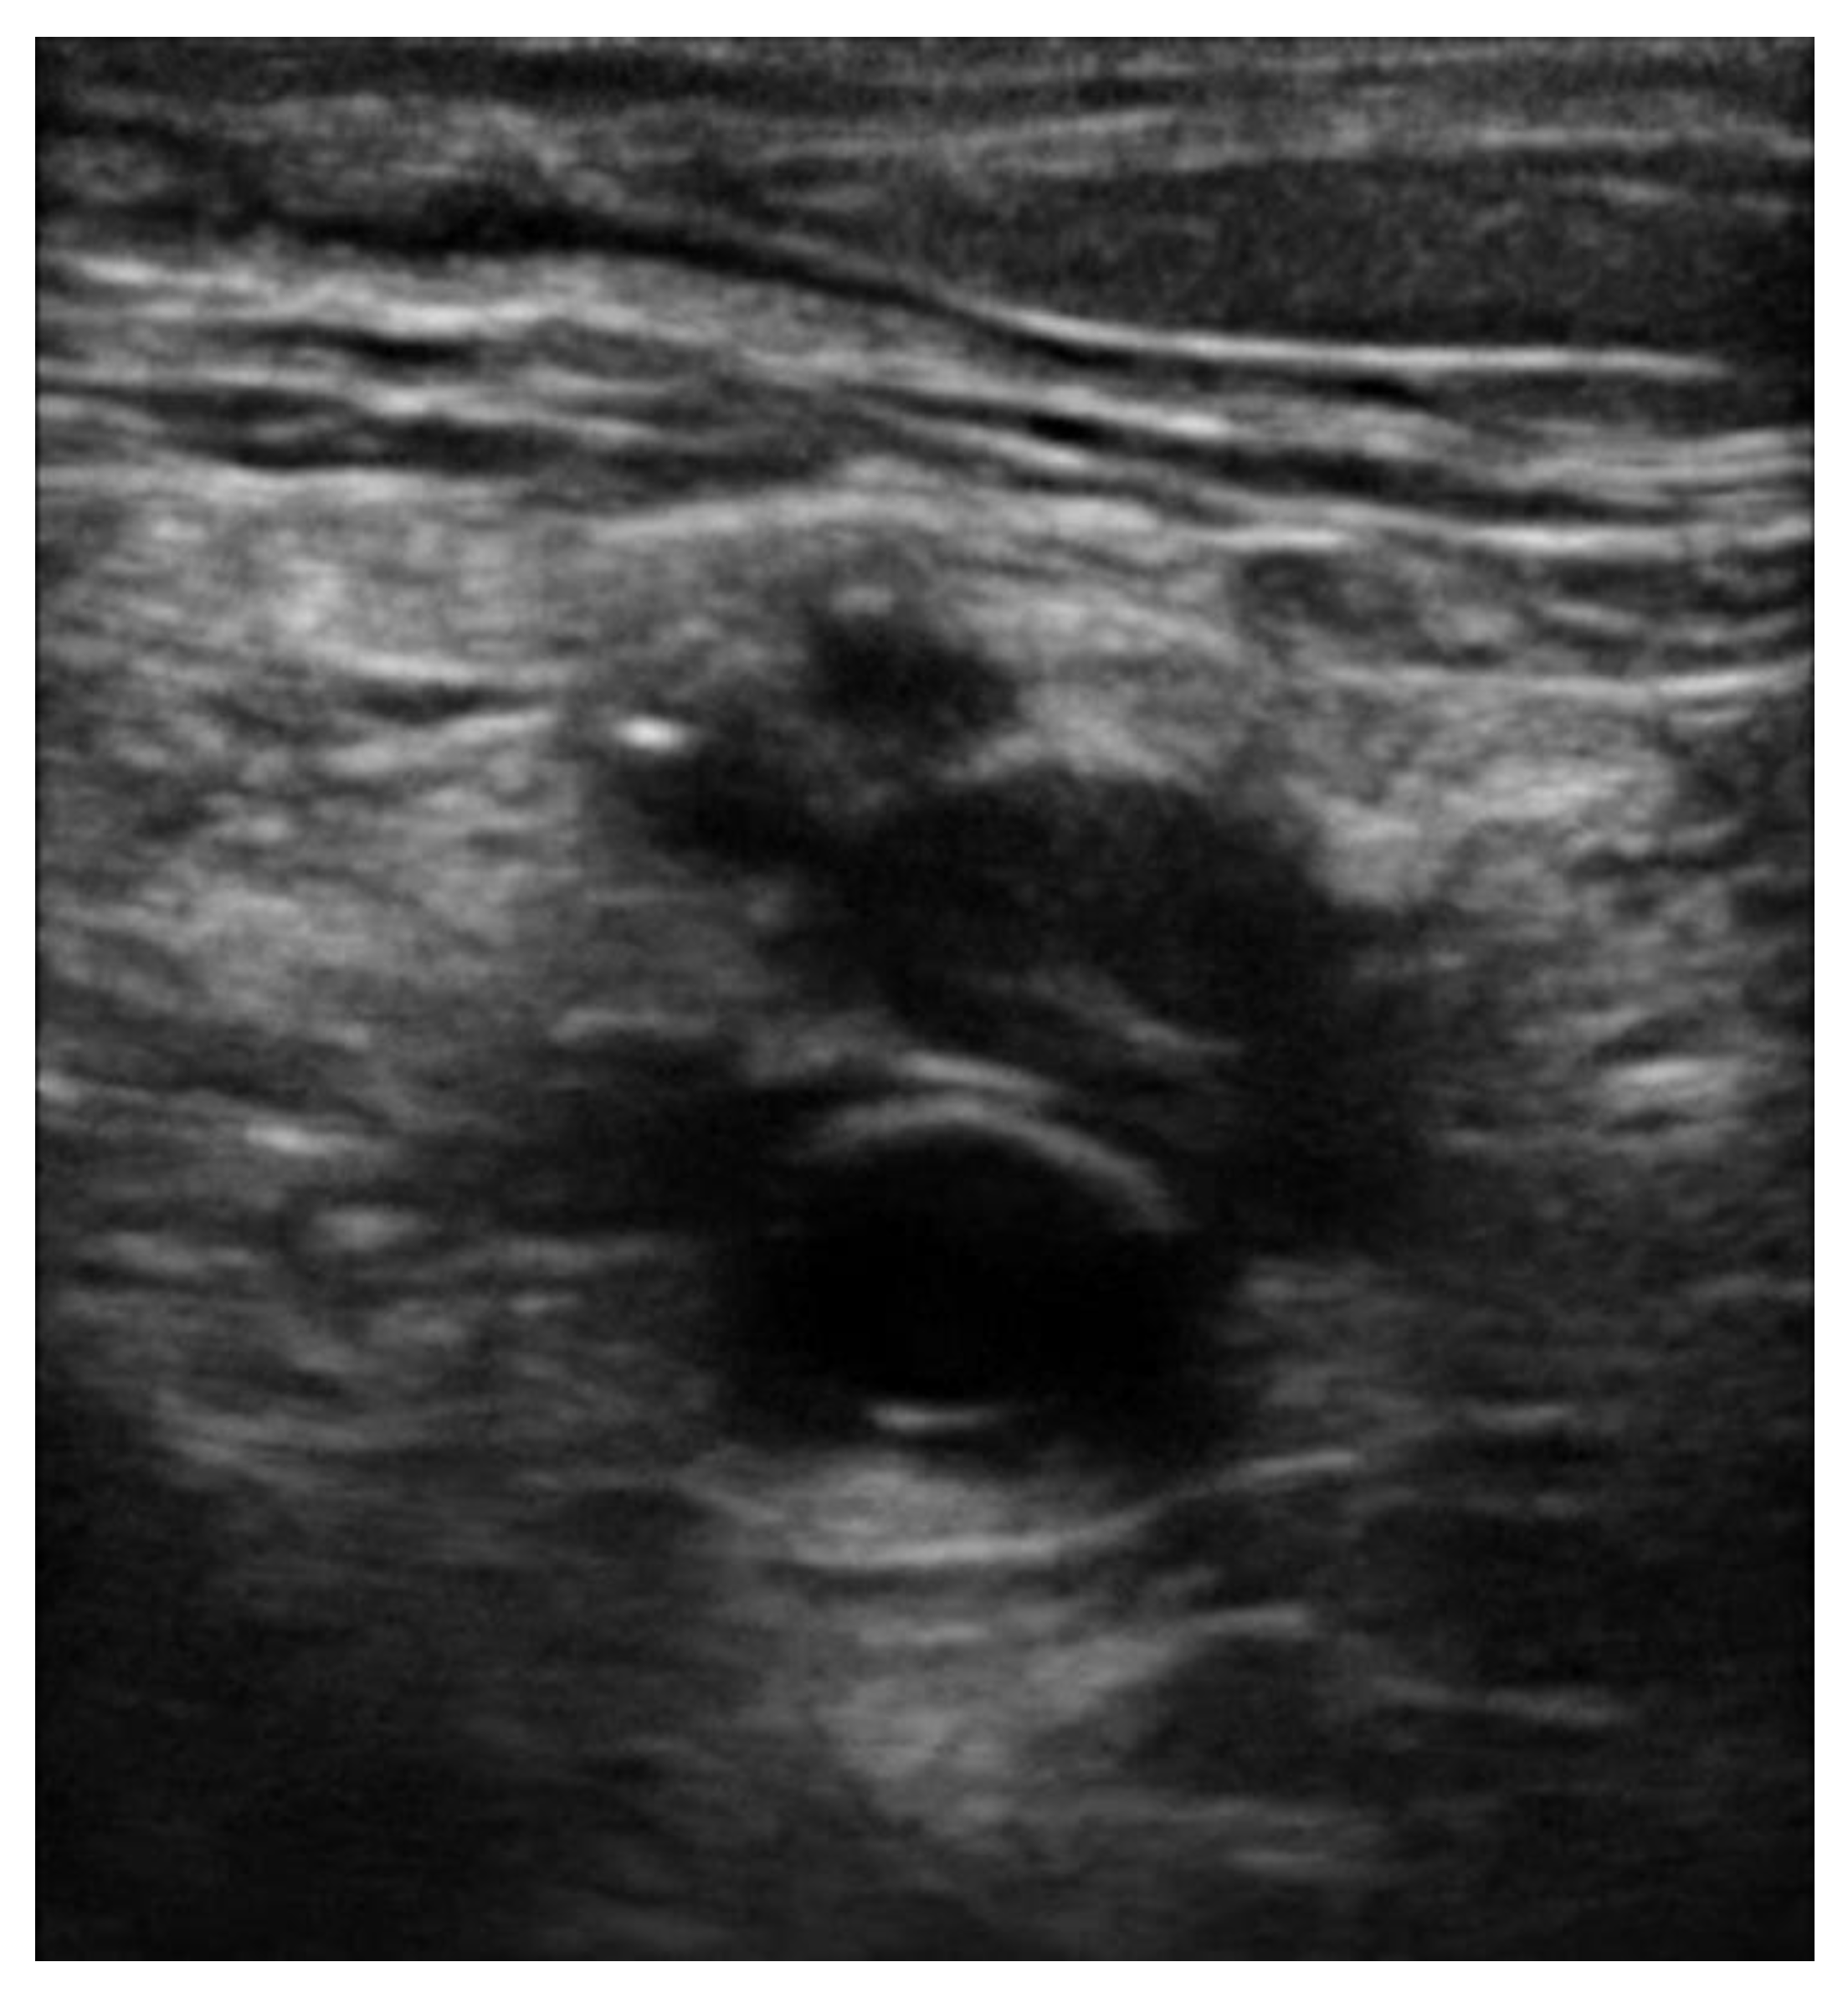

5. Protocols